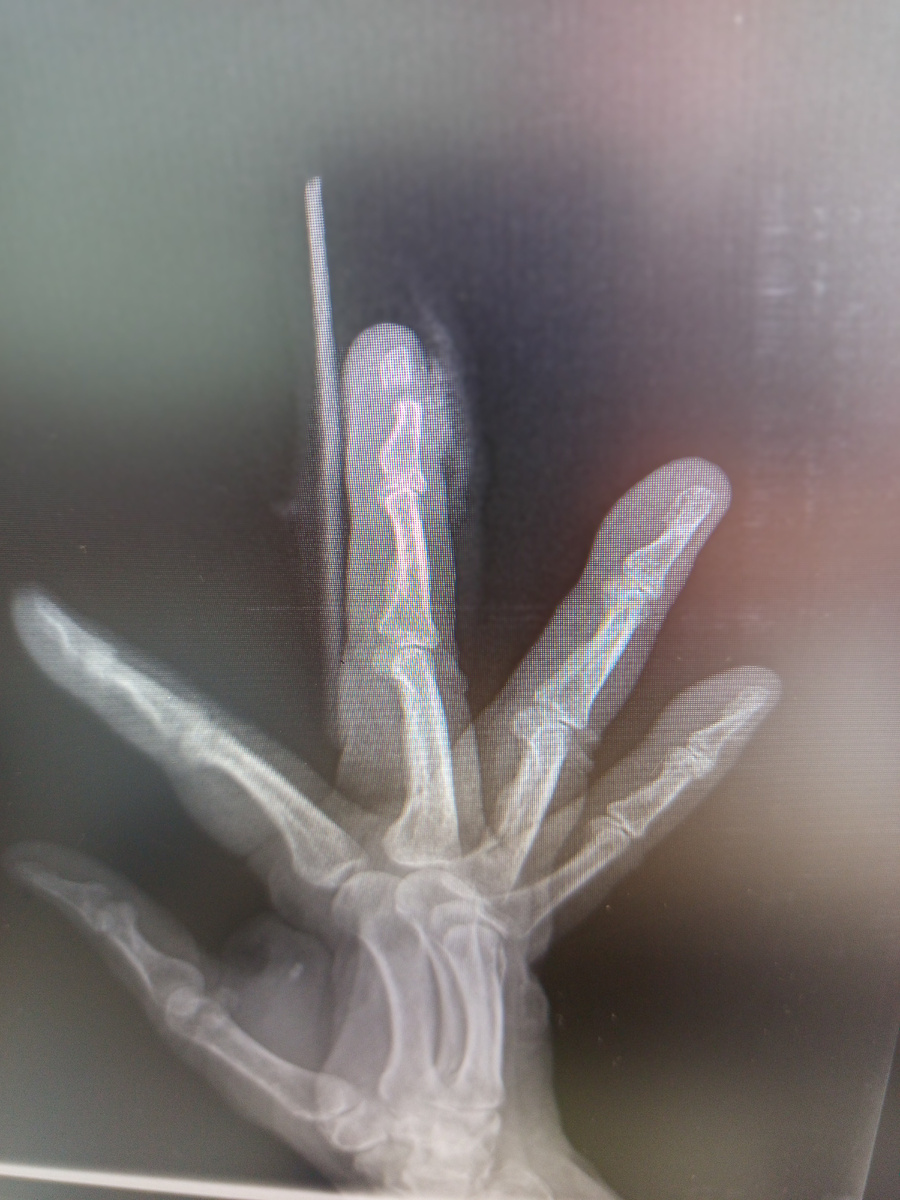

Женщина , 63 года пришла на снимок кисти , третий палец перебинтован.

–Палец дверью прищемила,-пояснила она. –Пришлось скорую вызвать.

На спицу не собирали , так гипс наложили на два пальца и прислали на контроль.